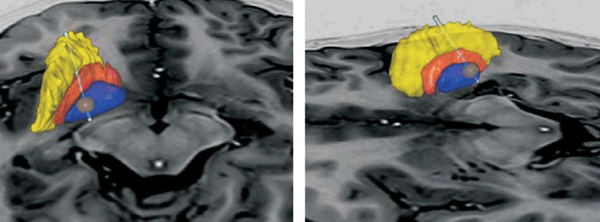

En el posoperatorio, el paciente evolucionó sin complicaciones y fue dado de alta a domicilio al tercer día. Luego de una revisión monopolar de contactos e impedancias se inició la estimulación con corriente continua (amplitud 2 mA, frecuencia 130 Hz, ancho de pulso µs. Se efectuó una tomografía computada de control que fue fusionada a las imágenes de resonancia con el software SureTuneTM (Medtronic MN, USA) para corroborar la posición correcta de los electrodos dentro de ambos GPi (Figura 3).

Figura 3: Se observan reconstrucciones 3D del núcleo lenticular derecho e izquierdo (GPi en azul, globo pálido externo -GPe- en anaranjado, putamen en amarillo). Los electrodos se identifican bien posicionados dentro de la parte posterior del GPi. La esfera marrón representa el volumen de tejido activado (VTA) por la estimulación eléctrica con los parámetros seleccionados.